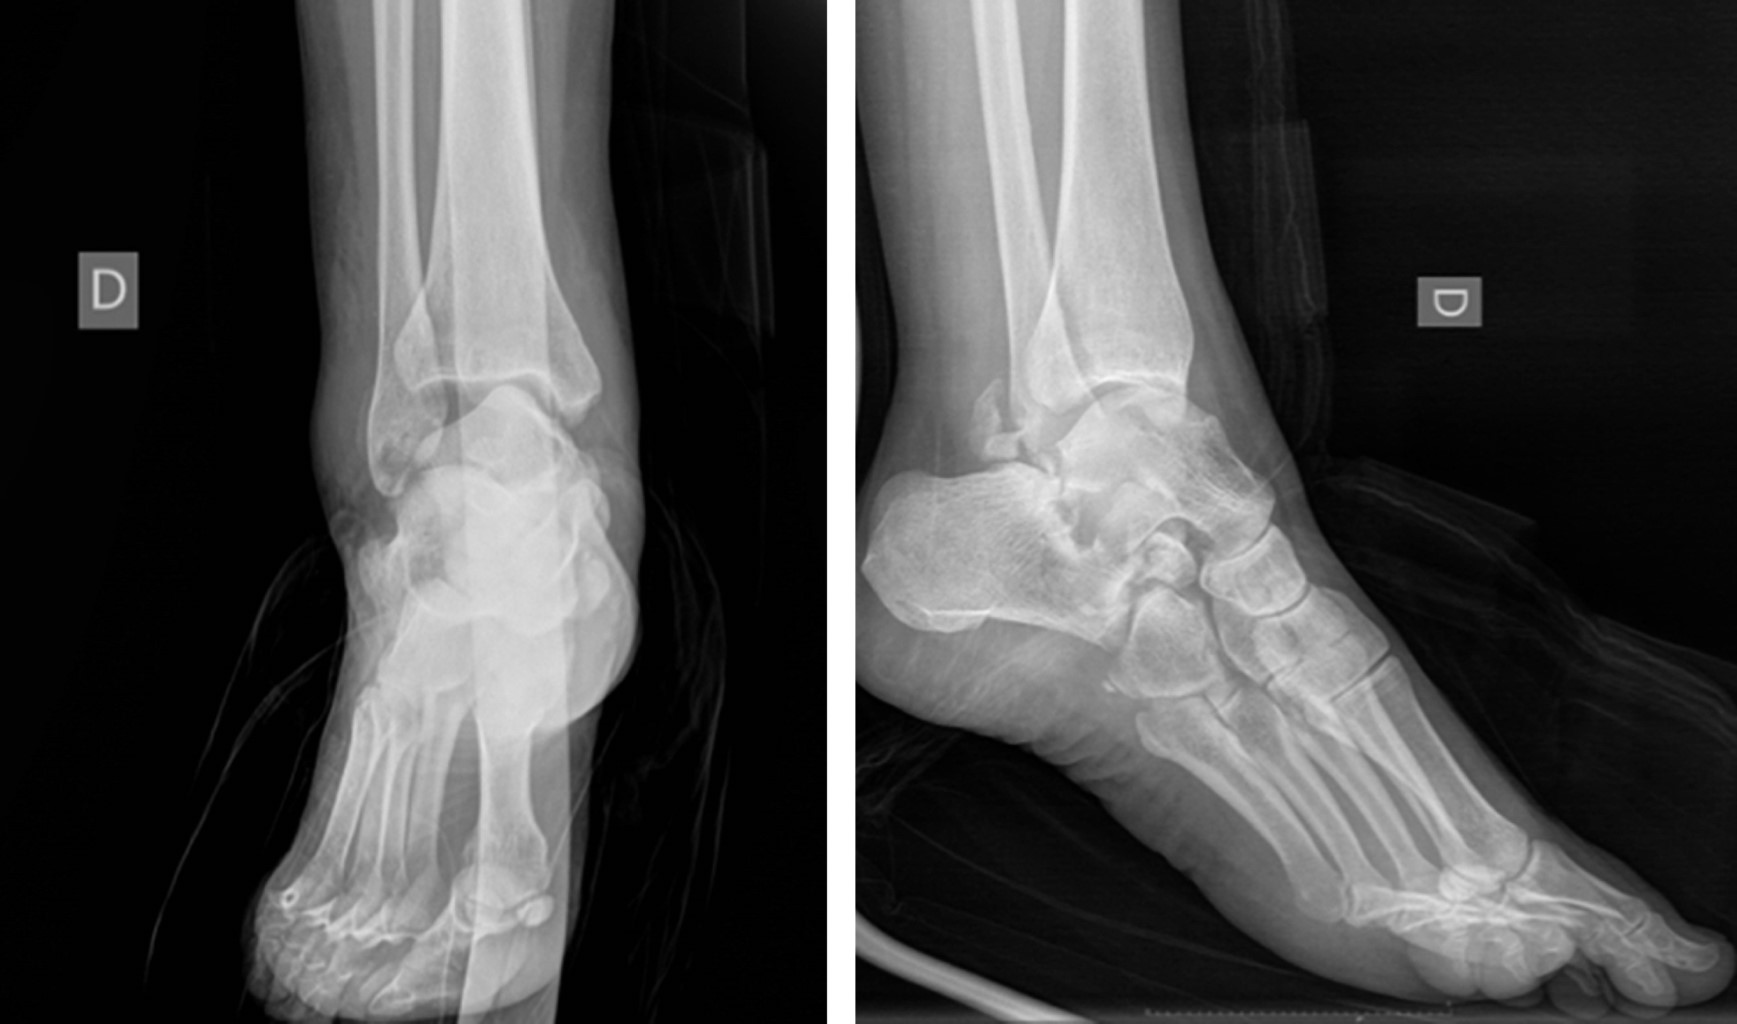

Introduction: subtalar dislocations, typical of high-energy trauma, are classified as medial, lateral, anterior or posterior depending on the deviation of the foot in relation to the talus. Lateral dislocation accounts for 17% of the total and has a worse prognosis. Immediate reduction is required to reduce the risk of sequelae, the incidence of which is around 90%. Objective: a case of lateral subtalar dislocation is presented; a review of the literature on its diagnosis, treatment and prognosis is carried out. Clinical case: a 46-year-old woman fell from a height of 3 meters, with severe deformity in the hindfoot. There was good distal vascular coloration, but no pulse or posterior tibial sensitivity could be identified. In addition, she had a medial sulcocutaneous fold under the head of the talus. Plain radiograph and CT revealed lateral subtalar dislocation, with fracture of the sustentaculum tali, and a "fleck sign" in the posterior region of the distal fibula. Suspecting soft tissue incarceration, a medial approach was performed, observing interposition of the posterior tibial neurovascular bundle. After joint reduction, the sustentaculum tali and the "fleck sign" were osteosynthesized. In addition, a complete section of the long lateral peroneal tendon was identified, which was tenodesed to the short peroneal tendon. Finally, an external fixator was placed. After eight weeks, the fixator was removed and weight bearing was authorized; after six months, mobility was complete and hypoesthesia persisted only in the plantar pad. Conclusions: lateral subtalar dislocation is an uncommon entity with a poor prognosis. Adequate interpretation through a thorough examination and pre-reduction CT of the bone and soft tissue lesions minimizes future sequelae.

Figure 1

Figure 2